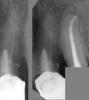

Hermit Опубликовано 1 ноября, 2007 Автор Поделиться Опубликовано 1 ноября, 2007 Четвёрка только меня смущает... 5 и 6 можно попробовать перелечить. Если получится пройти каналы, то Каласепт я бы поставила на 1-2 недели. Хотя лично мне (но это именно лично мне ) больше нравятся пасты типа Витапекс. Их тоже имеет смысл ставить на 1-2 недели. Дольше держать их бесполезно, всё равно динамика (положительная или отрицательная) на снимках будет видна не ранее, чем через 6 месяцев. Поэтому каналы можно пломбировать и ставить вкладки, но всё это без гарантии. Петерку переличил. Не знаю, хорошо ли. Врач сказала, что каласепт достаточно поставить на 4 дня, т.к. он быстро теряет свои антисептические свойства. За апекс что-то выходит. Возможно гуттаперчивый штифт. Скажите пожалуйста, это опасно или нет? При снятии снимка с пятерки в кадр попала и четверка. Поскольку неятно, что такм у нее сбоку, то привожу здесь снимок пятерки вместе с еще парой снимков четверки. Может по поводу них что-то еще прояснится. Ссылка на комментарий

Максич Опубликовано 2 ноября, 2007 Поделиться Опубликовано 2 ноября, 2007 Петерку переличил. Не знаю, хорошо ли. Врач сказала, что каласепт достаточно поставить на 4 дня, т.к. он быстро теряет свои антисептические свойства. За апекс что-то выходит. Возможно гуттаперчивый штифт. Скажите пожалуйста, это опасно или нет? При снятии снимка с пятерки в кадр попала и четверка. Поскольку неятно, что такм у нее сбоку, то привожу здесь снимок пятерки вместе с еще парой снимков четверки. Может по поводу них что-то еще прояснится. [/quote Что вывели за апекс штифт, не есть очень хорошо. Опасно или нет? время покажет Ссылка на комментарий

Снежана Опубликовано 7 ноября, 2007 Поделиться Опубликовано 7 ноября, 2007 А можно, если зуб будет продолжать болеть, перелечить зуб, притом, так, чтобы вынуть штифт из-за апекса? Не думаю, что его нужно перелечивать, при распломбировании канала есть риск протолкнуть штифт еще дальше за верхушку. Если зуб будет упорно продолжать болеть лучше обратиться к хирургам и сделать резекцию. Ссылка на комментарий